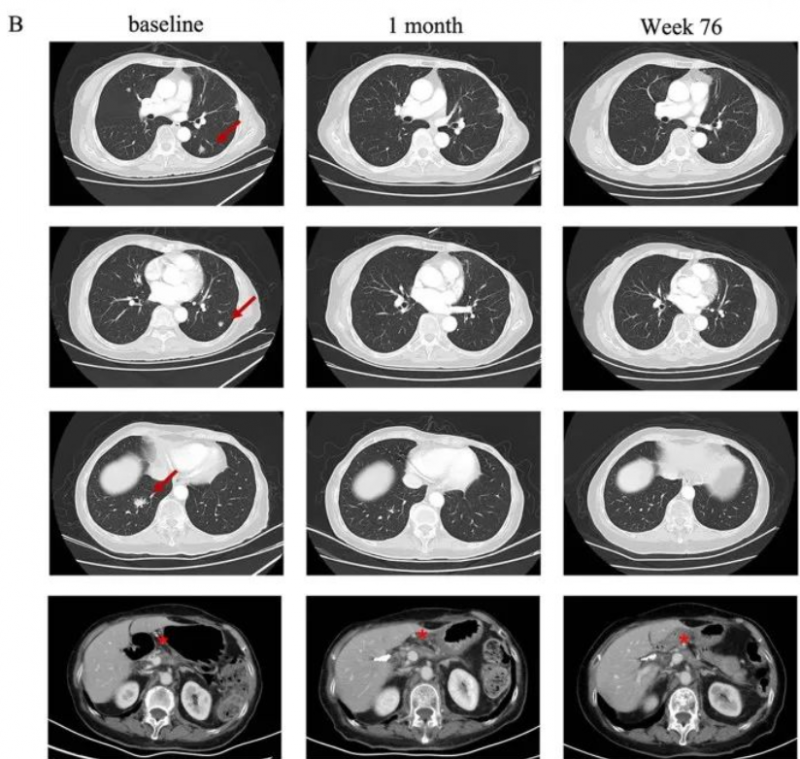

一名75岁的高龄女性胰腺癌患者,于2019年5月接受了手术切除,诊断为pT2N0期胰腺癌。术后随访5个月时发现肺转移。自2019年12月开始一线S-1单药化疗,在行手术野姑息性放疗期间肺部转移。经检测其Claudin18.2表达为3+/60%后入组CT041临床试验。

在进行氟达拉滨、环磷酰胺、白蛋白紫杉醇方案清淋预处理后,患者于2021年7月输注CT041细胞输注。输注后患者出现2级CRS,经托珠单抗治疗后恢复。患者在CT041输注后第4周进行首次肿评即达到部分缓解(PR),后肺部靶病灶进一步消失达到完全缓解。截至2023年7月末次随访时患者仍处于持续缓解状态。